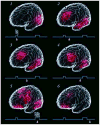

Working memory is critical to the integration of information across time in goal-directed behavior, reasoning and language, yet its neural substrate is unknown. Based on recent research, we propose a mechanism by which the brain can retain working memory for prospective use, thereby bridging time in the perception/action cycle. The essence of the mechanism is the activation of 'cognits', which consist of distributed, overlapping and interactive cortical networks that in the aggregate encode the long-term memory of the subject. Working memory depends on the excitatory reentry between perceptual and executive cognits of posterior and frontal cortices, respectively. Given the pervasive role of working memory in the structuring of purposeful cognitive sequences, its mechanism looms essential to the foundation of behavior, reasoning and language.